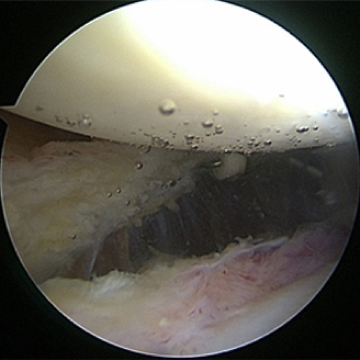

관절내시경 수술 전

관절 내시경 수술 후

노화된 어깨의 관절낭을 절제해 간격을 넓혀주는 수술방법

ㆍ환자 동의를 받은 자료이며, 이미지 사진은 실물과 다를 수 있습니다.

ㆍ2016.09.30 관절내시경 당일 치료 전, 후 사진입니다.